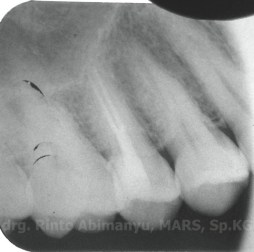

Kemudian diambil juga foto ronsen dari gigi itu, ini hasilnya..

Dari ronsen terlihat memang kavitas meluas sampai di bawah permukaan oklusal dan mengenai pulpa, tidak terlihat kelainan di periapeks.